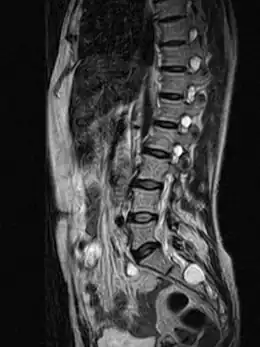

Un kyste de Tarlov (KT) ou kyste périneural, est une dilatation locale de l'espace sous-arachnoïdien se formant au contact d'une racine nerveuse, le plus souvent sacrée, dans la zone de transition entre arachnoïde et périnèvre (membrane externe du nerf). Il est fréquent et le plus souvent asymptomatique, mais peut parfois causer des symptômes neurologiques : on parle alors de maladie de Tarlov.

La cavité kystique correspond à une prolongation de l'espace sous-arachnoïdien entre l'endonèvre et le périnèvre. Dans la classification de Nabors (1988) les KT correspondent à des kystes de type II[2]. Génétiquement, ils sont rattachés à la famille des défauts du tube neural[3],[4].

Quel que soit le système de classification, la définition d'un kyste de Tarlov est histopathologique car elle nécessite la présence de fibres de racines nerveuses de la colonne vertébrale dans la paroi du kyste ou dans sa cavité. Les kystes de Tarlov sont définis comme des lésions sacciformes, remplies de LCS, situées dans l'espace extradural du canal spinal sacré et formées à l'intérieur de la gaine de la racine nerveuse au ganglion de la racine dorsale.